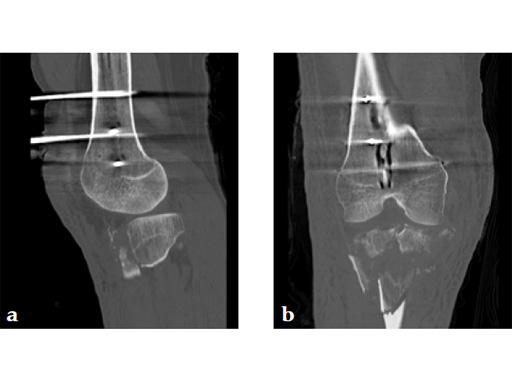

Staged management with initial rodding of femur and placement of spanning knee external fixator with closed manipulative reduction of tibial plateau (Fig 3).

The patient returned to the operating room once soft tissue allowed for open reduction and internal fixation of the tibial plateau fracture via a lateral utility and anteromedial approach. Placement of low bend 3.5 mm proximal tibia plate laterally and 3.5 mm locking T-plate anteromedially to buttress the impacted anterior rim (Fig 4, Fig 5).